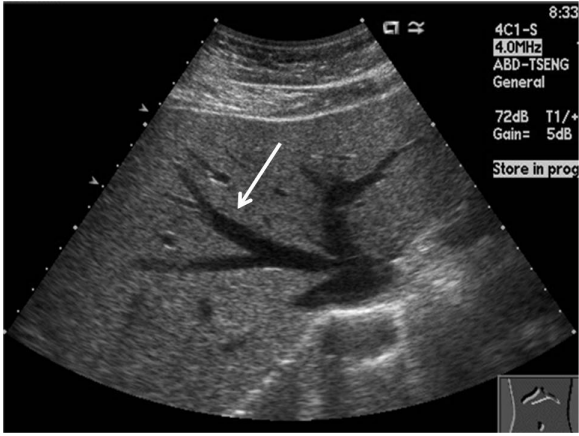

71.下圖為腹部之超音波影像,可能的變化為下列何者?

(A)膽管擴大 (B)肝囊腫 (C)肝腫瘤 (D)脂肪肝